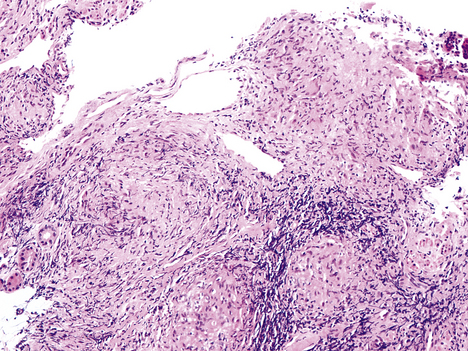

As indicated above, most secondary TB represents re-activation of old primary infection. These lesions are nearly always located in the lung apices, sometimes bilaterally (Fig. 14.11). Histologically, typical granulomas are seen, most having central zones of caseous necrosis. Progression of the disease depends on the balance between host sensitivity and organism virulence. Most lesions are converted to fibrocalcific scars, a frequent finding in the lungs of elderly people at autopsy. However, as in primary TB, many complications can ensue.

image

Fig. 14.11 Secondary pulmonary tuberculosis. Lung at autopsy showing cavitation and scarring at the apex of the right upper lobe.